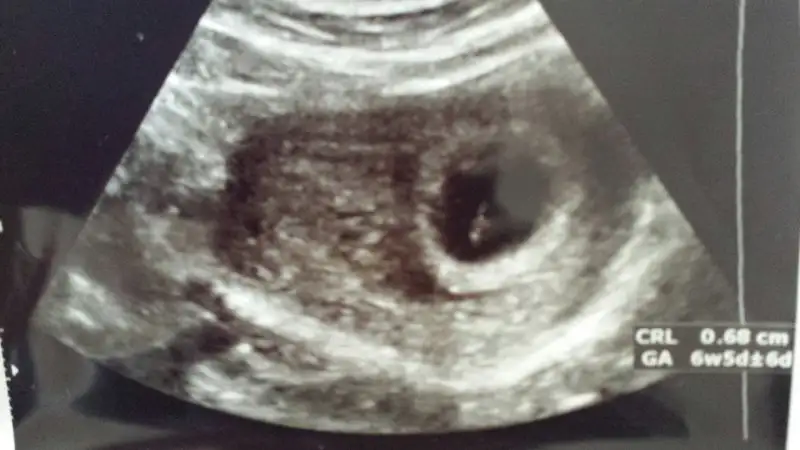

Kızlar benimde ultrasond kağıdıma bakarmısınız. Bebeğime karından bakıldı bugun çekildi. 7hafta 1 günlük hamileyim